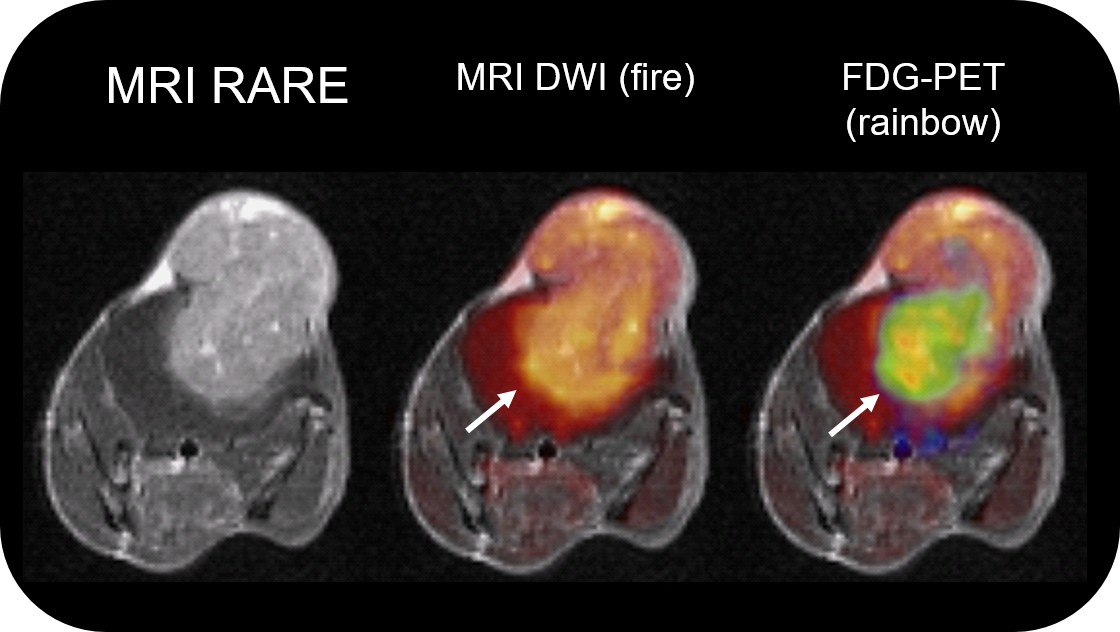

• Intuitive software package, for multi-dimensional MRI/MRS data acquisition, visualization, reconstruction, and analysis of MRI and/or PET/MR data

PET Insert or Inline

Upgradable with state-of-the-art PET module as inline or insert with full field of view and accuracy offers real, homogeneous sub-millimetric volumetric PET resolution and quantification in all three axes, in the entire field of view. This is possible due continuous crystal detectors with SiPM technology and true depth of interaction 3D precision equivalent to 10+ layer pixelated crystal detectors.